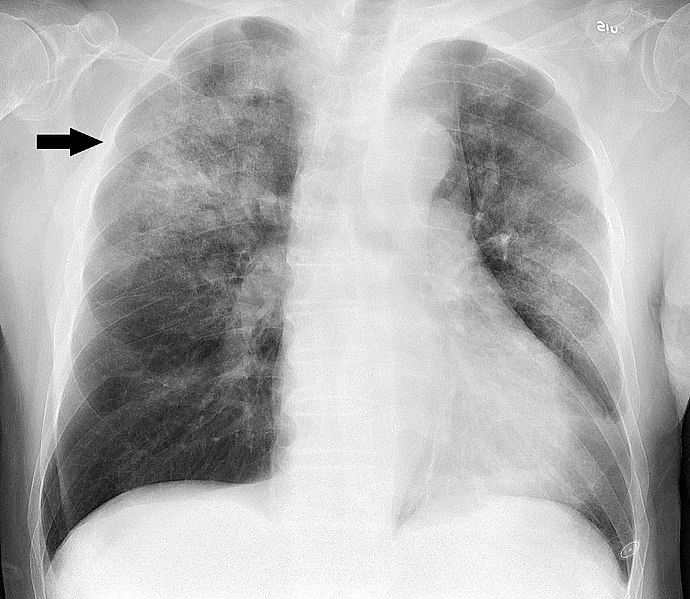

pneumonia chest ray influenza wikipedia patchy influenzae treatment lobe right upper pneumonitis wiki

pneumonia lungs consolidation radiographs children via bilateral antibiotic symptoms remedies natural vitamin naturalhealth365 treatment manifestation diagnosed rays lung tissue seen

lung chest infection pneumonia ray xray showing disease vitamin incidence term short cancers linked cancer progression pa childhood had higher